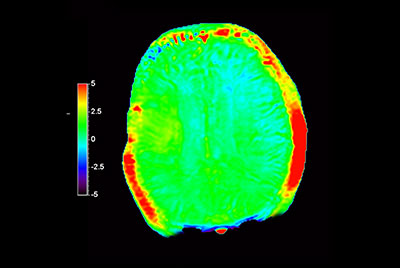

Myocardial infarction with T1/T2 Mapping